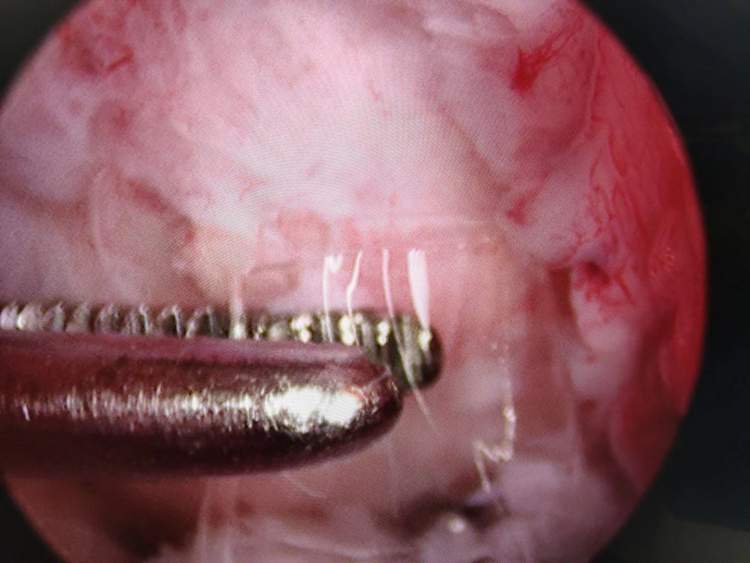

从镜子下看,当然患儿关节内的软骨及前十字韧带表面已经出现了损伤,考虑是被玻璃磨损及切割造成的,要是不将其取出或者再拖延段时间,肯定会造成更严重的关节内损伤,导致严重后遗症。通过仔细搜寻,顺利找到并取出了四块玻璃,都为透明状,最小的直径只有约1mm。

最后一块位于膝关节后方的玻璃难度最大,寻找了很久才发现一部分已经位于关节外,剩下的则包埋在了关节囊及滑膜内,只露出了很小的一段。将其取出后,再次为患儿的膝关节进行X光的检查,没有发现剩余异物残留,手术结束。